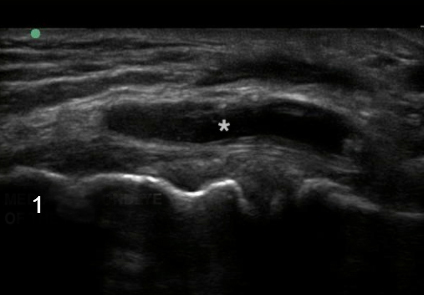

Knee Medial Meniscus Cyst Image

Asterisk: Cyst

Medial Epicondyle of the Femur